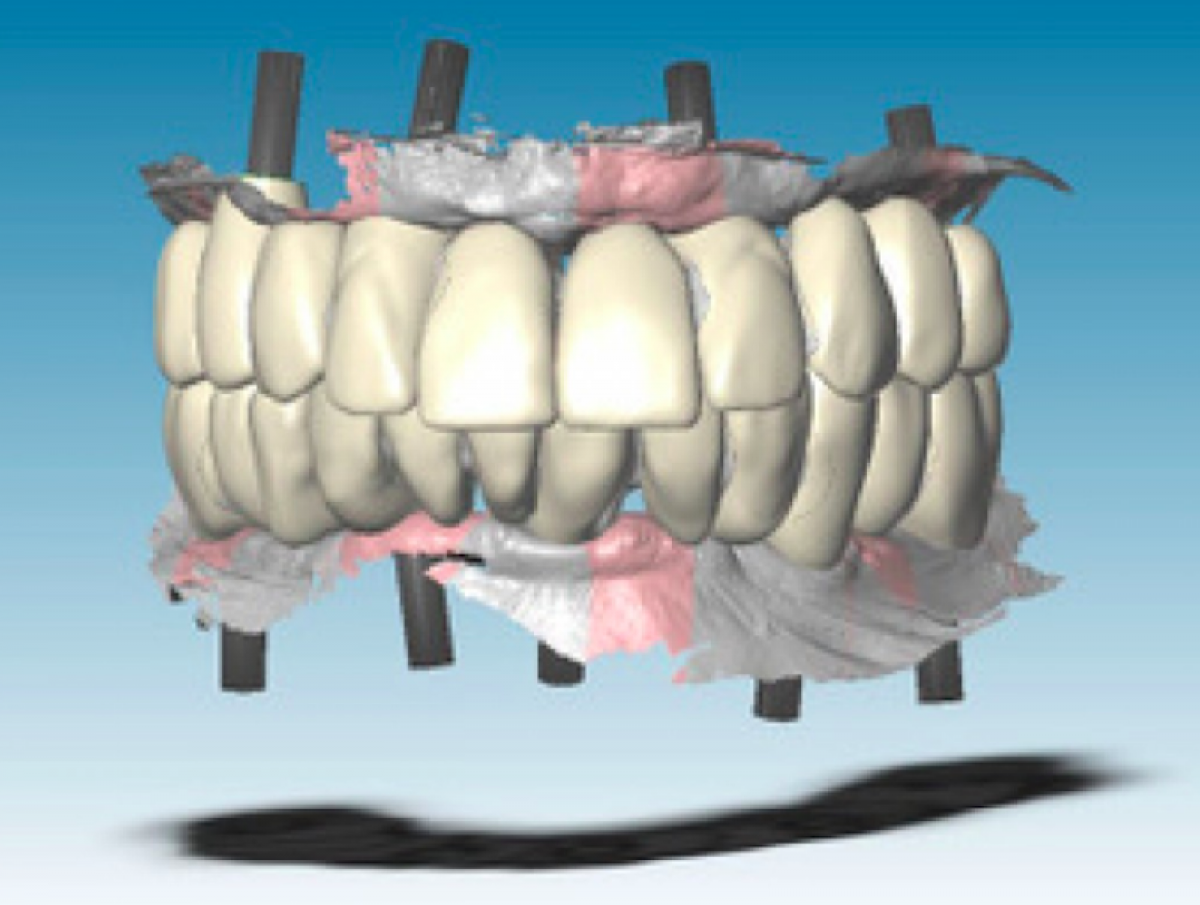

In this phase it is not possible to collect information about the occlusal relations between the two arches since there is no occlusal stop or stop. Finally, to collect the negative information about the soft tissues adjacent to the prostheses (implant emergence profile and gingival anatomy underlying the pontic elements), the upper and lower provisional were scanned outside the mouth and the third set of impressions ( STL3) was thus obtained. The three series of impressions STL1, STL2, STL3 were then imported into Geomagic Studio 12 software (3D Systems, Rock Hill, SC, USA) and combined using a specific automatic coupling algorithm. Since the gingival tissues scanned in the STL1 and STL3 series were the same, the software identified a good automatic coupling. Thereafter, the STL2 impressions were also coupled thanks to the correspondence between the form of the provisionals acquired in STL2 and STL3.Through the CAD union of the different fingerprints, a single file was obtained, called STL4, which contained the following information: three-dimensional scanbody position, soft tissue architecture, occlusal parameters and esthetic characteristics. The STL4 file was then imported into dental software (Dental Wings, Montréal, QC, Canada) to automatically and certify the position of the implants starting from the scanbodies (Figure 3).

The STL4 file, which at this point represented the virtual master model, was used to create two stereolithographic master models with the implant analogs. Also starting from the STL4 file, two aluminum bars (one for the upper and one for the lower one) with integrated implant connections (Figure 4) have been designed and made to CAD / CAM.

The digital design procedure was facilitated by the presence of the virtual wax-up of the final prosthesis (based on the form of functionalized temporaries) on STL4. This allowed the technician to draw the anchoring pins of the substructure based on the position of the teeth in the prostheses (Fig. 8).